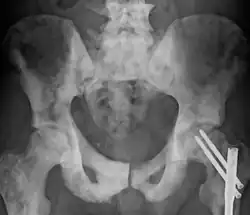

Sclerosis of the bones of the pelvis due to prostate cancer metastases

Osteosclerosis is a disorder characterized by abnormal hardening of bone and an elevation in bone density. It may predominantly affect the medullary portion and/or cortex of bone. Plain radiographs are a valuable tool for detecting and classifying osteosclerotic disorders.[1][2] It can manifest in localized or generalized osteosclerosis. Localized osteosclerosis can be caused by Legg–Calvé–Perthes disease, sickle-cell disease and osteoarthritis among others. Osteosclerosis can be classified in accordance with the causative factor into acquired and hereditary.[2][1]